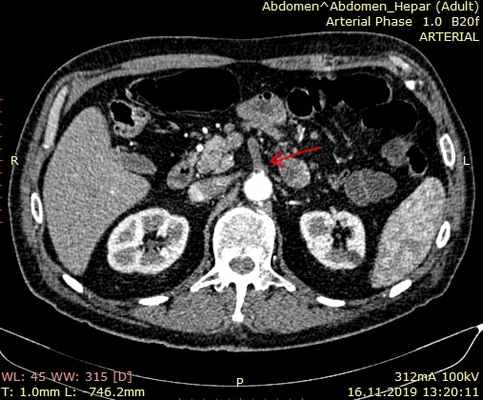

Мультиспиральная компьютерная томография с ангиографией

Мультиспиральная компьютерная томография аорты и ее ветвей позволяет точно оценить состоянии брыжеечных сосудов и помочь правильной постановке диагноза. Признаками острой мезентериальной непроходимости является отсутствие контрастирования брыжеечных артерий со слабым развитием коллатеральных сетей кровообращения. При соответствующих жалобах и клинической картине компьютерная томография позволяет поставить точный диагноз в большинстве случаев мезентериального тромбоза. Требуется внутривенное введение контраста и детальный анализ полученных изображений.